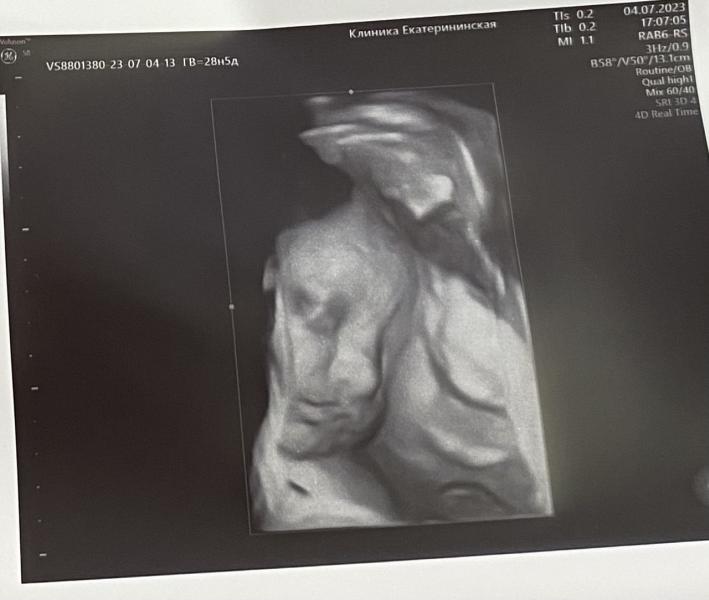

Евгения·Мама сына (1 год), беременна (33 нед.)

Когда уже будет наша встреча? Жду с нетерпением! Осталось совсем чуть-чуть, скоро увидимся!

Осталось совсем чучуть до нашей встречи💙